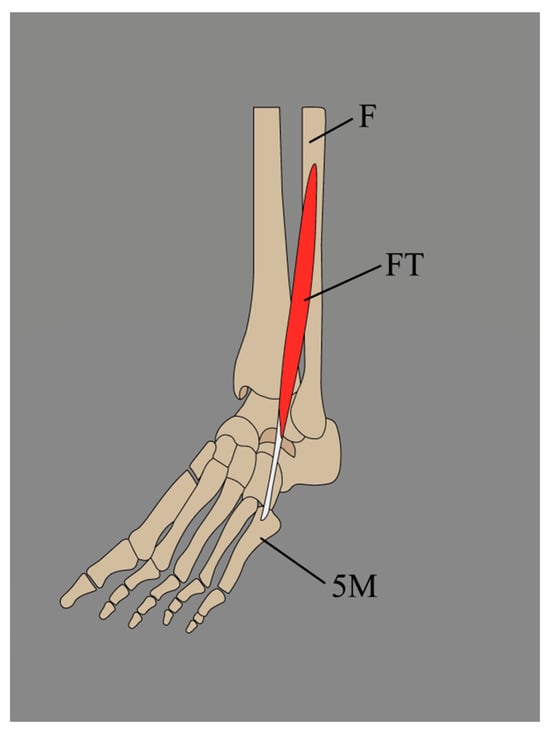

3.1. The Fibularis Tertius (FT) Typical Descriptive and Functional Anatomy

3.1.1. Typical Descriptive Anatomy

3.2.2. Variations in the Origin of the Fibularis Tertius (FT)